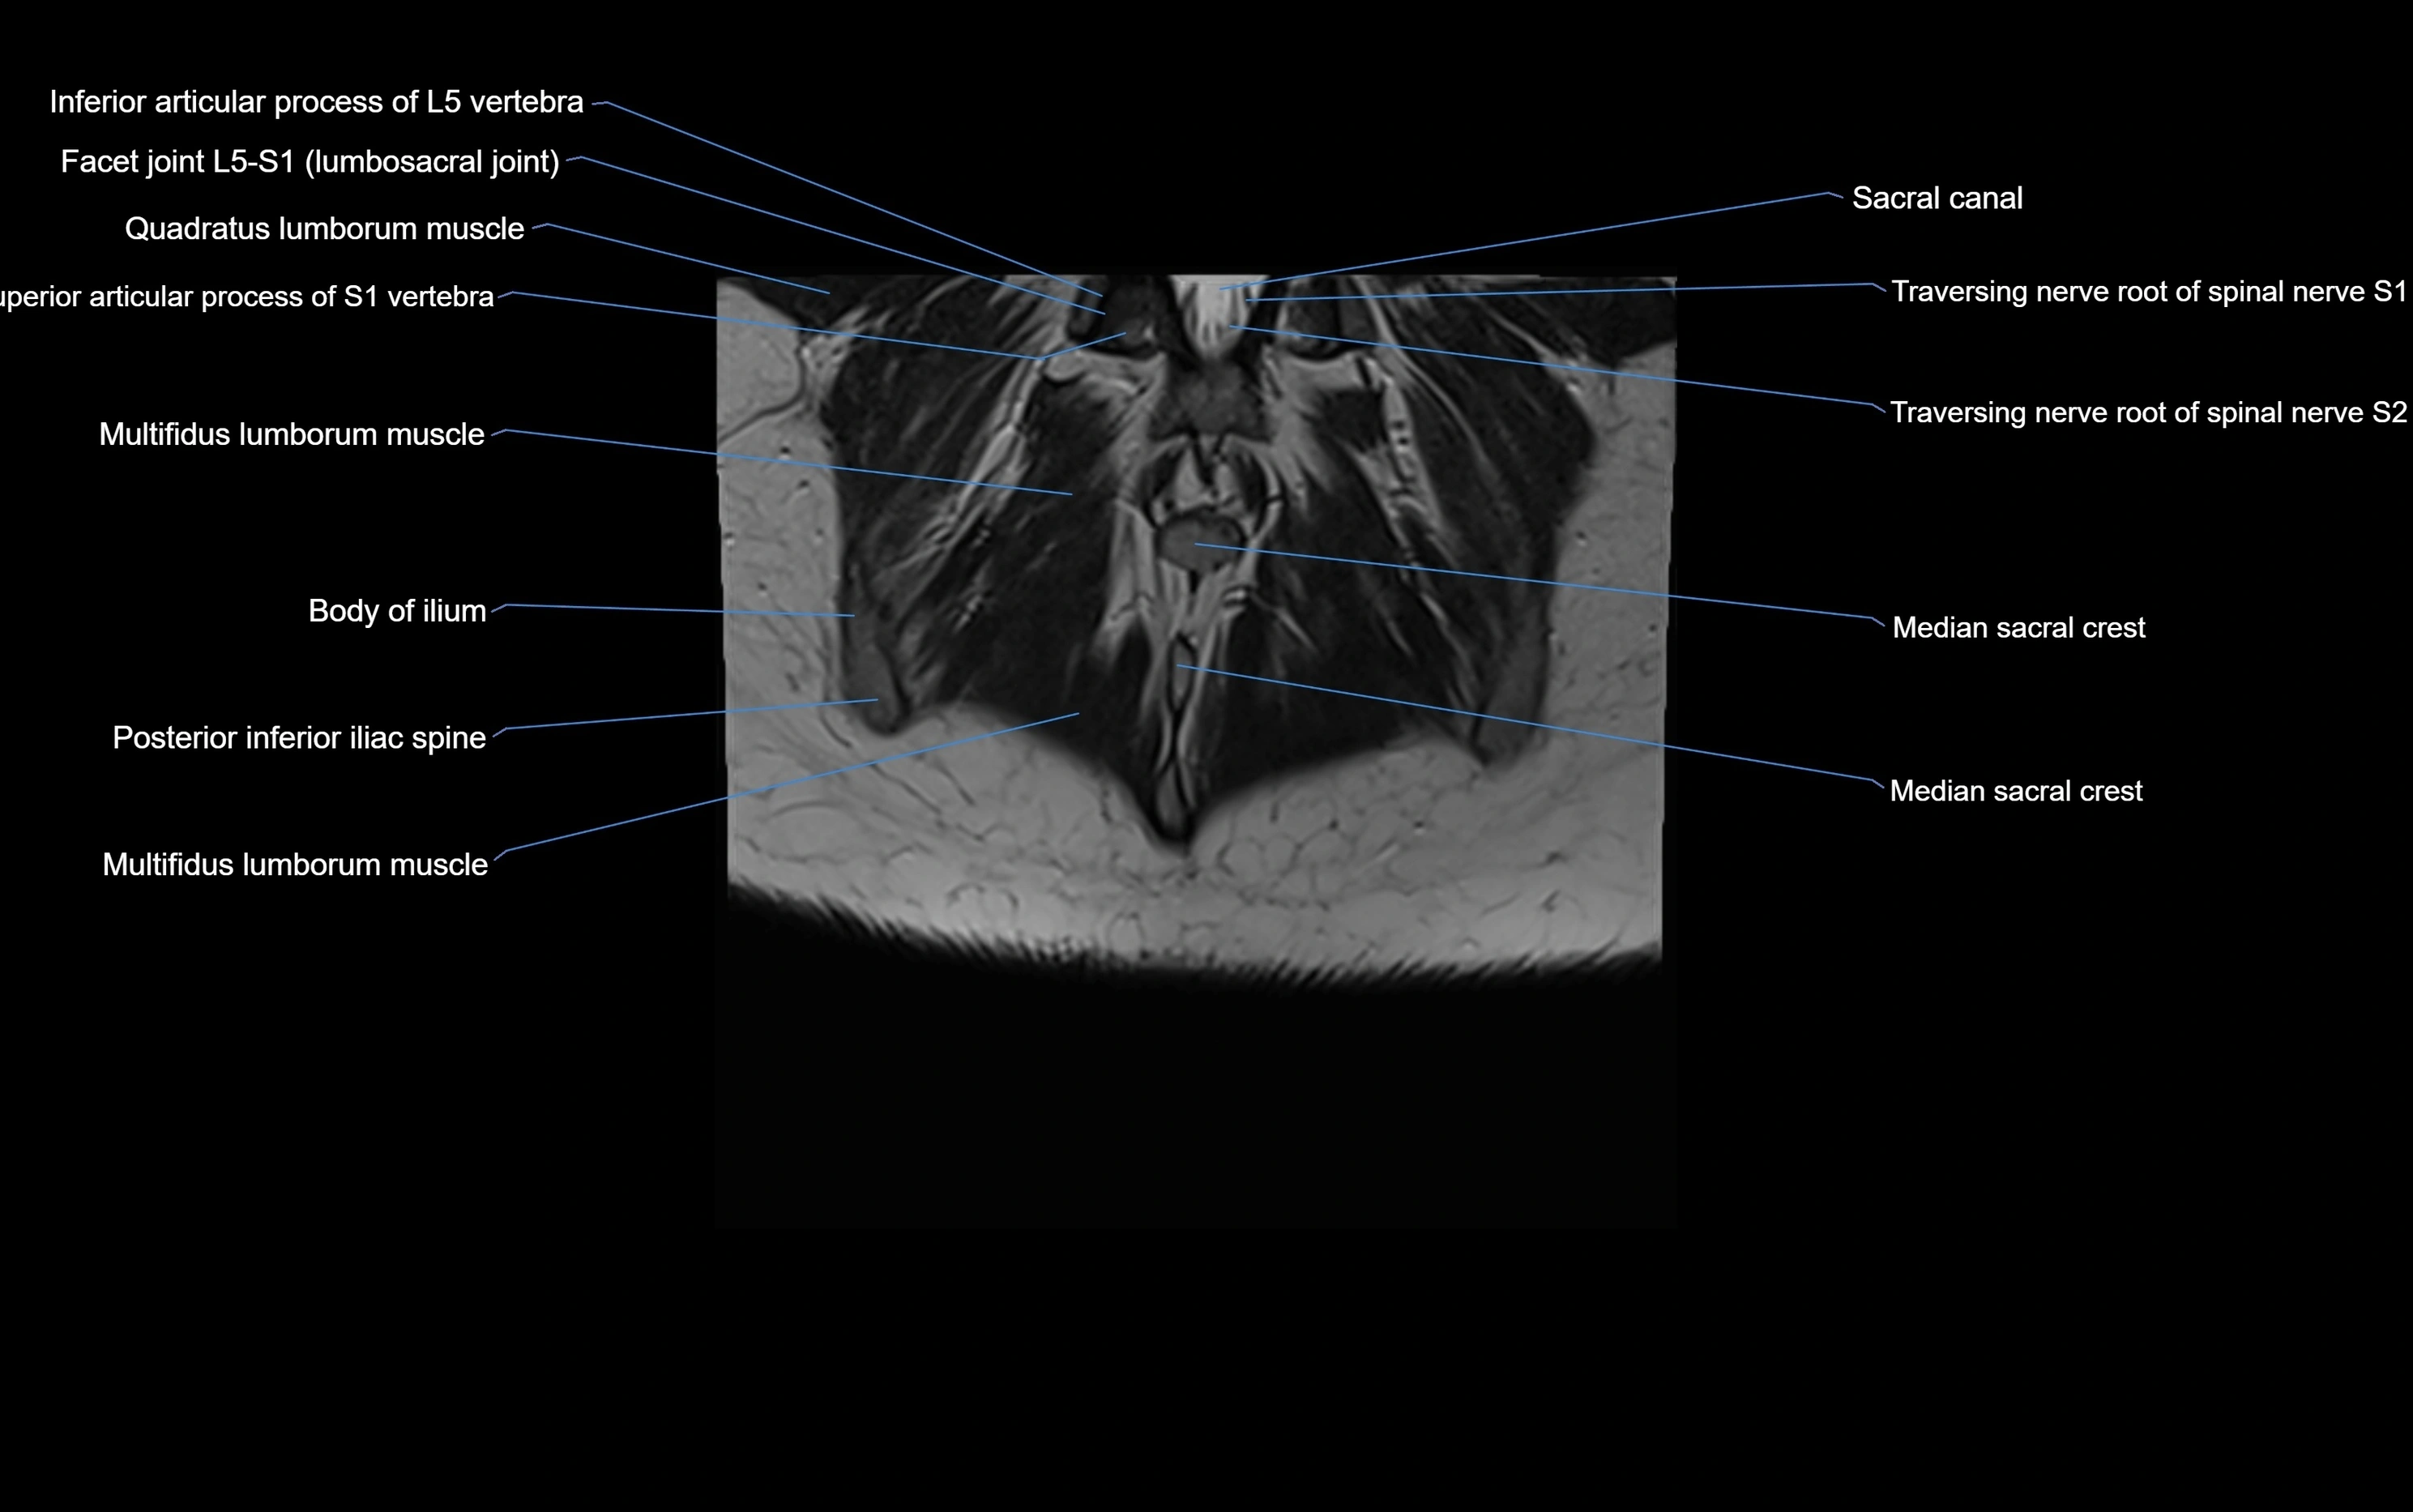

CT image

image